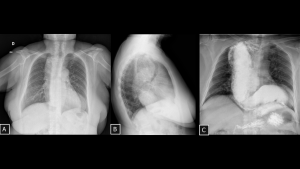

Fig 21: Case 22 – Megaesophagus:

Posteroanterior (A) and lateral (B) chest radiographs of a female patient with Chagas disease show mediastinal widening, anterior displacement of the trachea, and an elongated retrocardiac opacity. A barium oral contrast esophagogram (C) demonstrated a dolichomegaesophagus mimicking a mediastinal mass.

SYSTEMATIC APPROACH: 1. Age: Adults (e.g., Chagas, Achalasia). | 2. Morphology: Widened mediastinum with air-fluid level. | 3. Enhancement: N/A (Viscus). | 4. Relevant Anatomical Relationships: Visceral compartment; mimics a solid mass on non-contrast images.